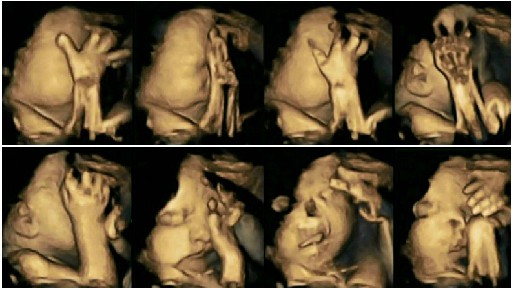

These remarkable images of a fetus holding his head shows us that smoking can harm the baby`s development. The ultrasound images show us that babies in the stomachs of mothers who smoke touch their face and lips more often than babies of non-smokers. As fetuses develop, they rarely touch their face but this 4D ultrasound showed that cigarettes can slow down the development of the baby’s central nervous system.

On the 4D ultrasound images you can see 2 fetuses, each one in the 32 week. The fetus above is from a mother who smokes and the other is from a non-smoker mother. The fetus carried by a mother who smokes constantly touches his face and mouth, which is an indication that his development is delayed.

M.D Nadia Raysland used these images to monitor the small movements in the womb. She monitored 20 mothers, from which 4 were smokers. After studying their images from weeks 21, 28, 32, and 36, she noticed that fetuses from the women that smoked moved their face a lot more than fetuses of non-smoking women.